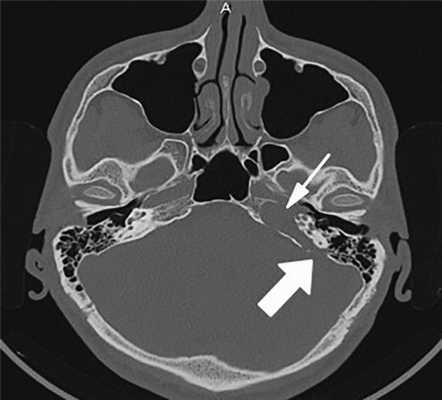

По результатам МРТ/РКТ височных костей: левая височная кость тотально заполнена патологическим субстратом с поражением пирамиды. Имеются деструктивные изменения височной кости: задняя грань пирамиды разрушена на протяжении 10 мм, передневерхняя — протяженностью до 15 мм, нижняя поверхность — до 25 мм. Капсула лабиринта значительно разрушена на уровне базального и среднего завитков улитки. Костная стенка лабиринтной части канала лицевого нерва не прослеживается, стенка тимпанального и мастоидального отделов сохранена. Отмечалось разрушение стенки канала внутренней сонной артерии. После внутривенного контрастирования не было отмечено деформации стенки сосуда.

Заключение: признаки рецидива холестеатомы пирамиды височной кости слева. Врожденная холестеатома?

Рис. 1. КТ пациента с холестеатомой левой височной кости — деструкция костной стенки внутренней сонной артерии (маленькая стрелка), базального и среднего завитков улитки, задней грани пирамиды (большая стрелка).